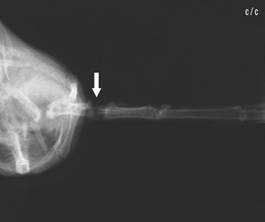

Radius fracture,

dislocated |

Radius fracture

after intramedullary pinning with a 0.4 mm

cannula |

The relatively frequent

radius fracture, which, if not treated, can lead to limited flight

ability, is pinned by using a 0.4 mm cannula, which is inserted into

the distal end of the fracture, exits through the radius head which

is palpable at the shoulder joint and is retrogradely pushed into

the proximal end of the fracture as far as just in front of the

elbow joint. The pin coming out at the shoulder joint is released 1

- 2 mm over the skin, and is protected with a small adhesive strip,